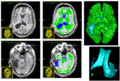

File:ABC-TBI-5.png

ABC-TBI-5.png (486 × 329 pixels, file size: 194 KB, MIME type: image/png)